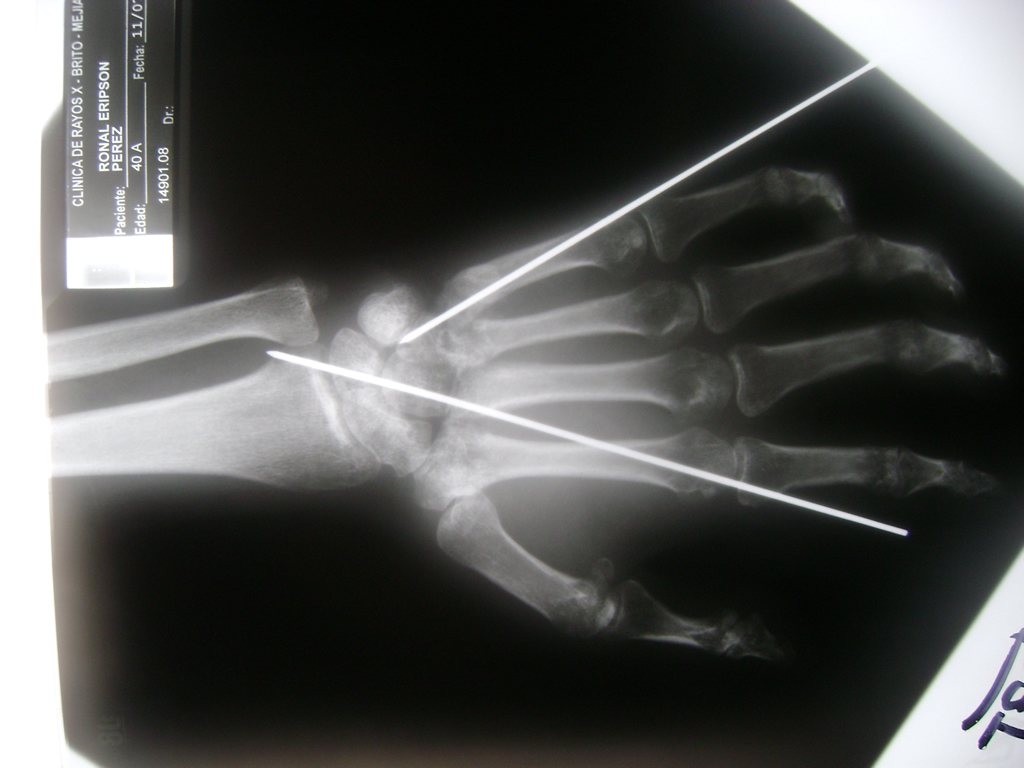

Los procedimientos más comunes en cirugía de la mano son aquellos destinados a reparar traumatismos, incluyendo lesiones de tendones, nervios, vasos sanguíneos, y articulaciones; huesos fracturados; y quemaduras, cortes, y otros daños de la piel.